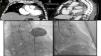

(A) Thoracic computed tomography angiogram, coronal view, showing the pseudoaneurysm and its entry site; (B) sagittal view illustrating a large heterogeneous pericardial fluid collection compressing the great vessels; (C) angiogram of the pseudoaneurysm; (D) closure device inside the pseudoaneurysm and distal disk positioned at the left ventricular wall. Ao: aorta; ICE: intracardiac echocardiography; LV: left ventricle; * pseudoaneurysm/closure device.

A transfemoral approach was used to cannulate the pseudoaneurysm (Figure 1C) and deliver the closure device, an Amplatzer Vascular Plug II™ (St. Jude Medical) (Figure 1D and Videos 1 and 2). At one-year follow-up, imaging confirmed complete cavity closure, device endothelization, and minimal pericardial effusion (Video 3).